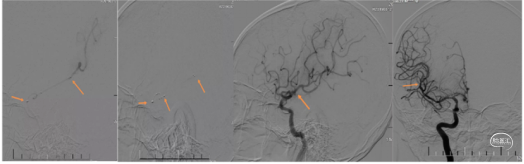

典型病例2 病例2 大脑前动脉血栓取栓

男,61岁,主因言语不清、左侧肢体偏瘫、小便失禁3天入院。入院查体:NIHSS评分=16分,GCS=3+3+4=10分。嗜睡,查体欠合作,思维、反应极迟钝,言语不利,右侧肢体活动可,肌力正常,左侧肢体肌力约1~2级,感觉轻度减退,左侧巴氏征阳性,右侧巴氏征阴性。

患者既往有高血压病史多年,心房纤颤病史多年,服用双抗、降脂药物,未用抗凝药物。由于1月前住院时发现右侧A2段狭窄,告知患者出现不适立即来院,所以此次发病后,患者直接来科室,要求机械取栓治疗。头颅CT无出血,直接进行DSA评估。

2.手术过程

(1)直奔主题,行右侧颈动脉造影,右侧A2原有狭窄处闭塞。下图1。

(2)左侧颈内动脉造影,左侧颈内动脉只供应同侧大脑前动脉、大脑中动脉不向右侧A2代偿供血下图2。

(3)微导管穿过右A2闭塞部位造影,提示A2以远通畅,下图3.

(5)决定取栓1次取出少许血栓,但取栓后造影,右侧A2仍然不显影。下图1、2

(6)微导丝穿过右A2闭塞部位,用2mm的球囊快速交换到达狭窄部位,低压力扩张后造影,可见右A2原有狭窄明显改善。下图3、4

7)把4mmX20mm的solitaire FR支架覆盖A2狭窄部位并解脱支架,造影可见右侧大脑前动脉完成再通,TICI3级,原有狭窄完全消失。下图5